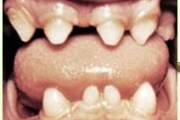

Hambaanomaaliad

muutused hammaste kujus